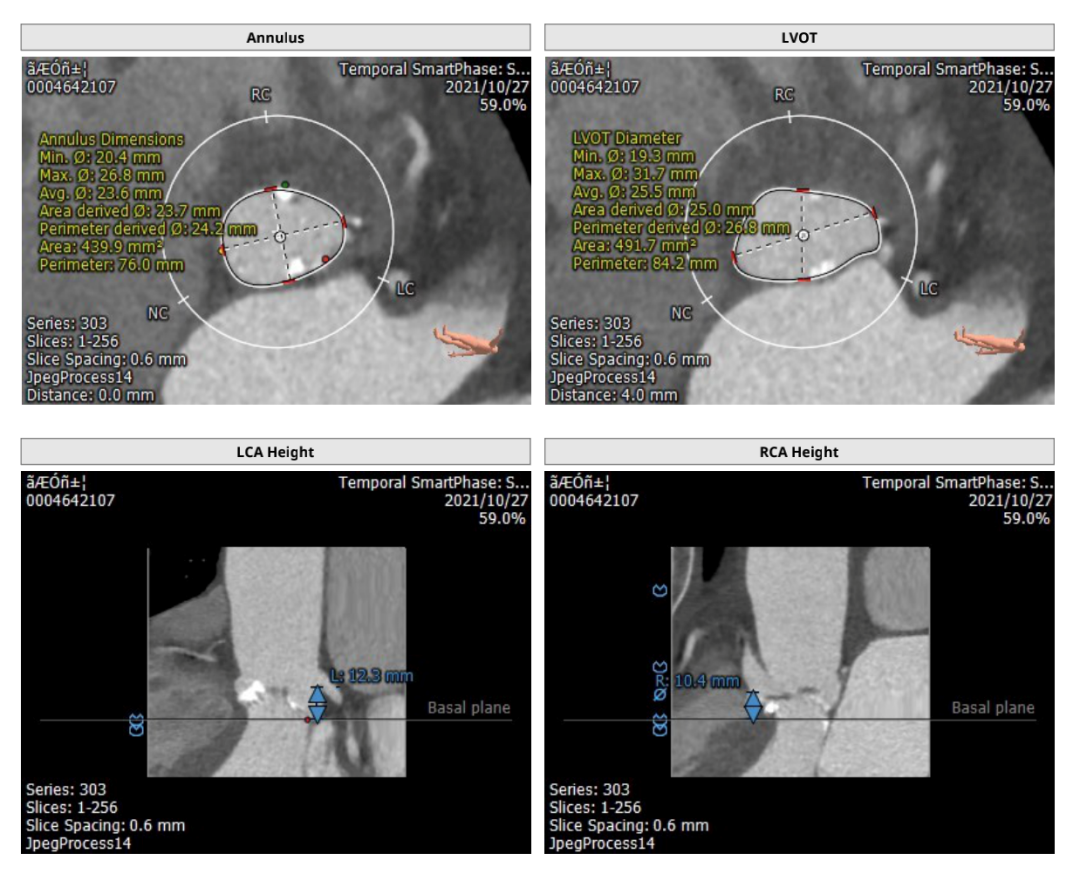

主动脉CT

主动脉根部及瓣环形态

瓣膜不同钙化程度,及形态

瓦氏窦瘤形态

入路条件

该患者是严重心衰伴瓦氏窦瘤患者,同时伴有瓣叶增厚,瓣环周长经为23.8mm,左右冠高度为13.8mm和18.9mm,在瓣膜选择上需要非常谨慎。经过团队讨论决定,预装VitaFlow Liberty™ 27瓣膜。